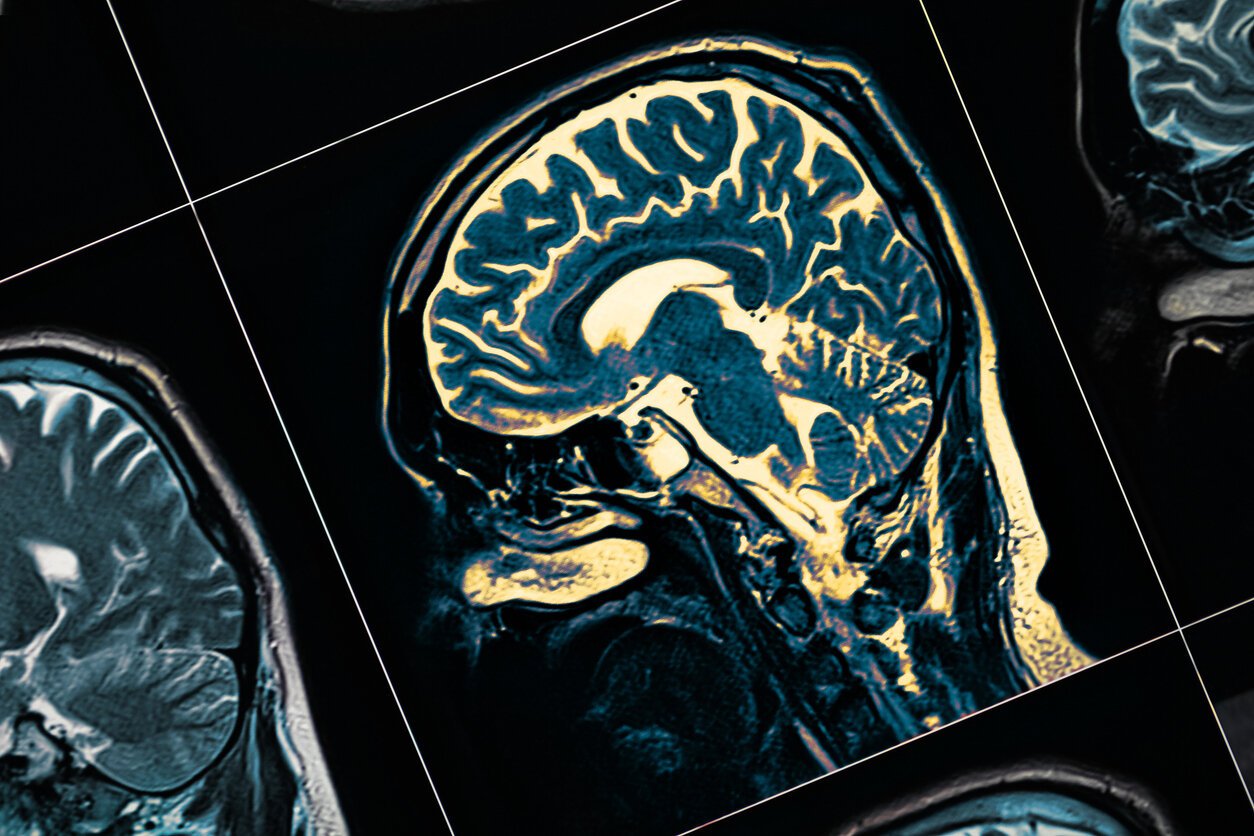

Cette maladie est provoquée par une diminution de la production de dopamine au niveau cérébral : un neurotransmetteur impliqué dans le contrôle de nombreuses fonctions comme les mouvements volontaires, la cognition, la motivation et les affects.

Dans leur travail de recherche, les neuroscientifiques ont découvert que la lumière infrarouge, acheminée par fibre optique au centre du cerveau, agit sur les photorécepteurs des mitochondries des cellules de la substance noire qui produit la dopamine. "Ces dernières sont revigorées par cette énergie lumineuse, suppose-t-on, car elles produisent à nouveau de la dopamine", explique le professeur Chabardes au média, Le Monde.

Cette fibre optique est reliée à un boîtier qui est implanté en surface du crâne lors d’une intervention chirurgicale. Le boîtier transforme ensuite l’électricité en lumière infrarouge. Celle-ci sera transportée par une fibre optique jusqu’aux cellules de la substance noire pour relancer la dopamine.